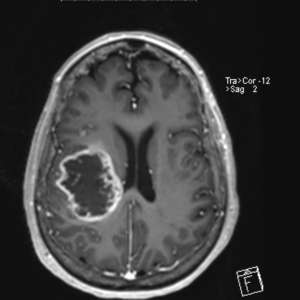

My symptoms were worse yesterday, so I went to the 2nd neurosurgeon's hospital and had another MRI. My glioblastoma is twice as large as itt was 2 months ago. No, that's not good news. The rest of my life will be in a hospital bed. But I'm upgrading to a better one. Pull-ups, Purewicks and Chucks from now on (look it up).😂